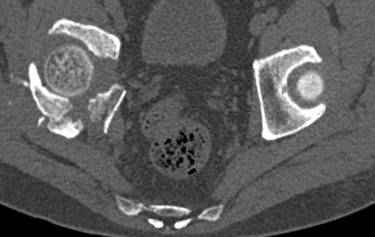

Интересно было бы посмотреть рентгенограммы до операции. У меня впечатление, что я не все вижу, что тут есть... Уважаемые Господа "тазисты" и "тазологи", к какому типу переломов вертлужной впадины по Летурнелю вы бы отнесли это случай?

Из переломов проходящих через крыло и/или заднюю стенку ни простой перелом "передней колонны" (явно имеется пером задней стенки, и не видно перелома седалищной или лонной), ни простой "поперечный", ни ассоциированный "Т-образный" (т.к есть перелом крыла и не видно перелома седалишной), ни ассоциированный "задняя колонна+задняя стенка", на ассоциированный "поперечный+задняя стенка", ни ассоциированный "передняя колонна+задняя гемисфера" (не видно перелома седалищной), ни ассоциированный "обе колонны" (не видно перелома лонной седалищной) не подходят под эту классификацию....

к таковым себя не причисляю, но...обычное дело для нашей страны - выкладывать 3D и не показывать стандартные проекции Judet. Дигност представляет те ракурсы, которые по-его мнению наиболее информативны, более того комп сам достраивает какие-то мелкие повреждения по 3D по своему усмотрению. По данной реконструкции можно предполагать высокий двухколонный перелом с оскольчатыми передней и задней колоннами, оскольчатую высокую переднюю колонну с задним полупоперечником или одно из перечисленных с вовлечение КПС. У меня впечатление за второй вариант, но нужно обследовать нормально - проекции, сканы.

высылаю дополнительно сканы.

итак, второй вариант: высокий двухколонный с вовлечением КПС... Ни одно из основных повреждений не репонировано, кроме задней стенки. Скорее всего попытка реконструкции вертлуги сейчас будет очень травматичной и не очень эфективной, т.е. вероятный риск более значим, чем ожидаемая польза... Лучше подождать, и потом сразу эндопротез